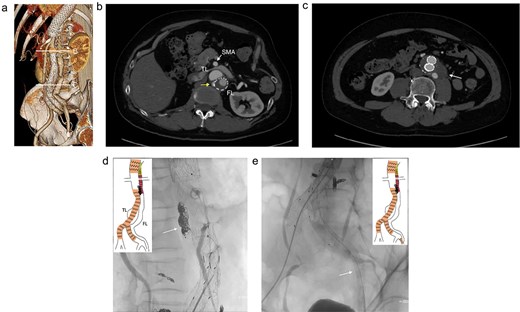

At 2-year post-procedure, CT follow-up showed AAA expansion to 56 mm, and FL dilation to 25 mm. The contrasted CT showed small inflow to the FL from the TL through the gap between the intimal flap and the FL stent graft via a residual intimal tear, as well as reversal flow from re-entry at the EIA (Fig. 2a–c). A second-stage endovascular repair was planned for completing the TAAA repair. Under local anesthesia, the gap between the FL stent graft and the intimal flap was occluded using DELTAFIL (Jonson & Jonson, NJ, USA) from FL side to close a residual intimal tear (Fig. 2d). The eighth intercostal artery and the third lumbar artery were occluded using DELTAFIL and GARAXY G3 (Jonson & Jonson, NJ, USA), respectively to block the backflow from these side branches. Then the 8 × 59 mm VBX (WL Gore & Associates, Newark, DE, USA) was deployed at left EIA covering the re-entry tear, successfully completing FL closure (Fig. 2e). The postoperative course was uneventful, with no paraplegia, and he was discharged on the postoperative day 4. The postoperative contrast-enhanced CT showed no contrast inflow into the FL. The CT imaging 3 years after the procedure showed the reduced diameter of abdominal aorta of 35 mm (Fig. 3a–c).

The contrasted CT 3D reconstruction 2 years after the false lumen (FL) stent graft placement (a; white arrow); the contrast-enhanced CT axial images showing small inflow to the FL from the true lumen through the gap between the intimal tear and the FL stent graft (b; arrow), and abdominal aortic aneurysm expansion to 56 mm (c; white arrow); the intraoperative angiography showing coiling of the gap between the intimal tear and FL stent graft (d; white arrow), and the VBX was deployed at left external iliac artery covering the re-entry tear (e; white arrow). TL: true lumen; FL: false lumen; SMA: superior mesenteric artery.